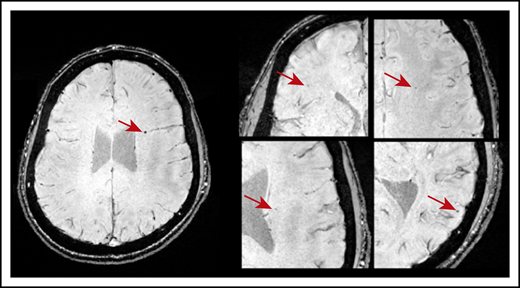

CMBs were identified in 21 of 49 patients with ITP (43%). Most CMBs were between 1 and 5 mm in diameter and variably distributed throughout the brain (Figure 1). Six patients (12%) had 1 CMB; 11 (22%) had between 2 and 4 CMBs; and 5 patients (9.8%) exhibited 5 or more CMBs. Fourteen of 33 patients younger than 45 years had CMBs: 5 had 1 CMB and 9 patients had >1 CMB. Three of 8 patients in the age range of 45 to 60 years had CMBs; 1 had 1 CMB and 2 had >1 CMB. Four of 8 patients older than 60 years had >1 CMB. No CMBs were identified in any of the 18 healthy control subjects.

Axial SWI showing CMBs (indicated by the red arrows) in a patient who was diagnosed with ITP at age 10. This patient was 20 years old at the time of MRI and had a disease duration of 118 months and 5 CMBs dispersed throughout the brain.